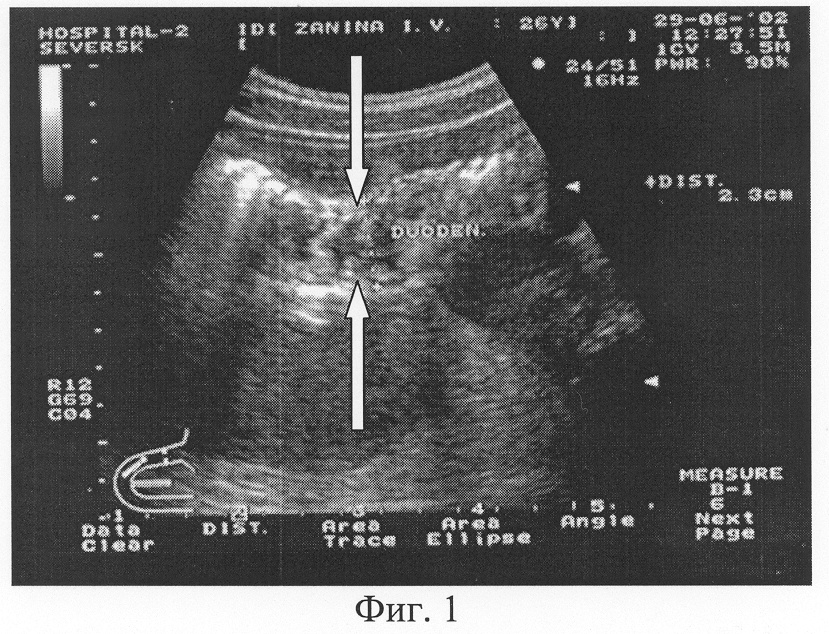

При изучении состояния стенки двенадцатиперстной кишки перед исследованием целесообразно назначить бускопан или аэрон для расслабления гладкой мускулатуры кишечника. Первым этапом ультразвукового исследования является изучение двенадцатиперстной кишки натощак. Затем обследуемый должен выпить 500 мл жидкости температурой 25-35°С. Далее пациенту необходимо лежать несколько минут на правом боку, после чего исследование продолжают при положении вполоборота на правом боку (предпочтительно для изучения луковицы и нисходящего отдела), или лежа на спине, или при вертикальной позиции обследуемого. Визуализация двенадцатиперстной кишки начинается с определения антрального отдела желудка при продольном сканировании. Затем осуществляют поступательное движение датчиком латерально вправо до медиальной стенки желчного пузыря. Латерально и кзади, иногда вверх от пилорического канала регистрируется луковица двенадцатиперстной кишки. Если исследование осуществляют после приема жидкости при положении пациента лежа на правом боку, полости привратника и луковицы могут быть заполнены жидкостью. Сканирование осуществляют как продольно луковице двенадцатиперстной кишки, так и перпендикулярно ей. Следует обратить внимание на диаметр просвета, толщину стенки кишки, наличие в ней гипоэхогенных утолщений, дивертикулоподобных выпячиваний, деформаций кишки. Предпочтительно изучать стенку кишки в период релаксации, вслед за прохождением перистальтической волны. После регистрации дистального отдела верхней горизонтальной части и верхнего изгиба двенадцатиперстной кишки приступают к исследованию ее нисходящей части. Наилучшим ориентиром при этом является желчный пузырь, по отношению к которому нисходящая часть кишки обычно расположена медиально и кзади. Осуществляют продольное, косое и поперечное сканирование, располагая датчик в правом подреберье соответственно проекции желчного пузыря и медиалыю от него, осуществляя поступательные и качательные движения. При поперечном сканировании необходимо захватывать в поле зрения поперечное сечение желчного пузыря. Наиболее информативным является продольное сечение кишки (Фиг.1), когда можно оценить как состояние стенки, так и перистальтику с движением жидкости в просвете, т.е. моторно-эвакуаторную функцию. При исследовании нижней горизонтальной части двенадцатиперстной кишки датчик располагают косо-горизонтально, ориентируясь на дистальный отдел нисходящей части и нижний изгиб кишки, однако полезными могут оказаться также другие плоскости сканирования. Плоскость продольного сканирования нижнего горизонтального отдела кишки проходит ниже поджелудочной железы, по косо-восходящему направлению справа налево.

Фиг.1. Трансабдоминальное ультразвуковое исследование двенадцатиперстной кишки. Продольное (относительно оси желудочно-кишечной трубки) ультразвуковое сканирование верхней горизонтальной части двенадцатиперстной кишки. Наружное сечение ДПК составляет 23 мм, четко дифференцируются структура стенки и просвет кишки (стрелки). Определяется довольно выраженная складчатость слизистой, возможна визуальная оценка характера содержимого ДПК.